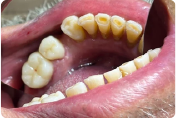

Paciente masculino de 72 años con una anatomía compleja debido a la ausencia de varias piezas dentales posteriores. El paciente presentaba coronas metálicas en los órganos dentarios 45 y 46 con filtración marginal, caries recidivante y una gingivitis localizada severa, producto del desajuste crónico de las restauraciones previas.

Presencia de caries recidivante y gingivitis severa causada por el filtrado marginal previo.

Tras la remoción, se observaron líneas de terminación poco visibles y una vía de inserción desfavorable debido a la retención en las preparaciones.